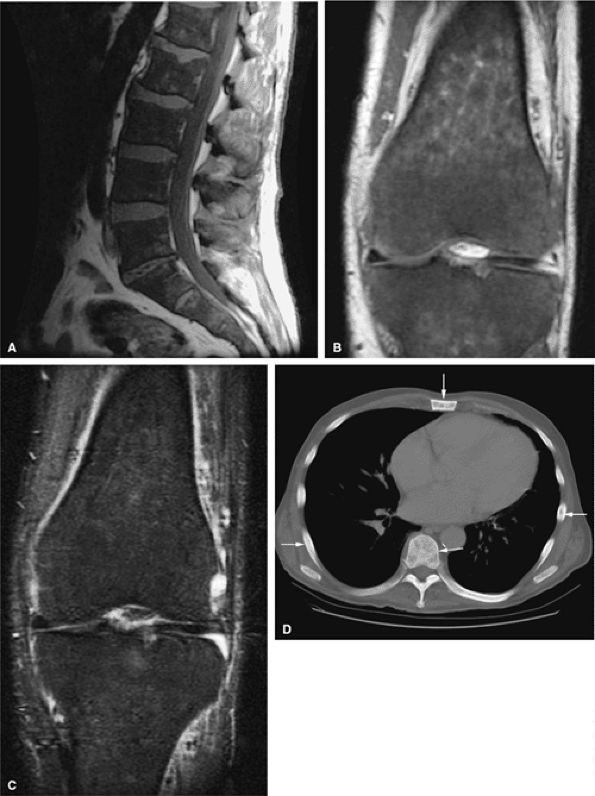

In primary myelofibrosis, T1-weighted images show patchy marrow involvement with low signal intensity on T1- and T2-weighted images (Fig. 13.20). With STIR techniques, the imaging characteristics of areas of involvement are identical to those of normal hematopoietic marrow (i.e., intermediate to mild increased signal intensity).57,58,59

FIGURE 13.20 ● Extensive myelofibrosis following chemotherapy for leukemia. (A) The bone marrow exhibits diffuse marrow fibrosis, which is of low signal intensity on a sagittal T1-weighted image of the lumbar spine. Low-signal-intensity myelofibrotic marrow is seen on these coronal T1-weighted (B) and fat-suppressed T2-weighted (C) images of the knee. (D) Abnormal sclerosis of the spine, sternum, and ribs is seen on the axial CT image (arrows).